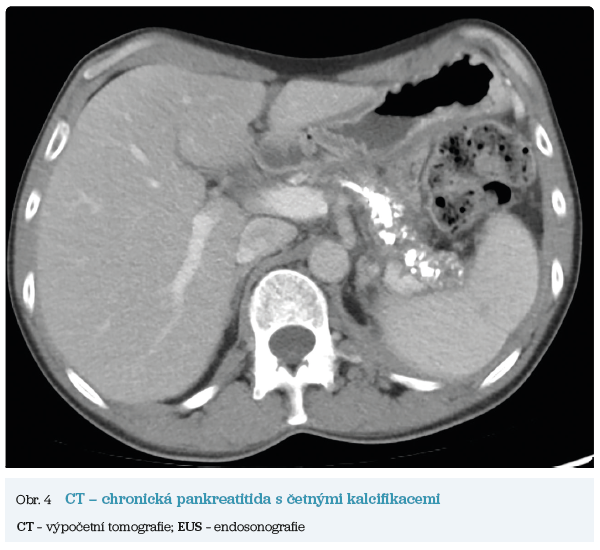

Několik studií se zabývalo AI asistovanou CT detekcí karcinomu pankreatu s AUC 0,79–0,99 %,6–8 tedy přesností porovnatelnou s přesností práce zkušeného radiologa. Stran časné detekce proběhla studie posuzující přesnost AI modelu v detekci karcinomu pankreatu v období 3–36 měsíců před prvními projevy onemocnění. Zařazeno bylo 155 pacientů s karcinomem pankreatu a 265 zdravých kontrol. AI model zde dosáhl AUC 0,98, což výrazně předčilo radiology, kteří při popisování stejných případů dosáhli AUC 0,66.9 Studie využívající DL model pro rozlišení zdravé slinivky od nálezu pankreatických neoplazií, tedy karcinomu pankreatu, intraduktální papilární mucinózní neoplazie (IPMN), serózních a mucinózních cystických neoplazií a solidní pseudopapilární neoplazie, byla prezentována s AUC 0,91, tedy opět odpovídající přesnosti popisu radiologa.10 Pro další vývoj a možné klinické využití bude potřeba přístupu k rozsáhlému archivu CT snímků karcinomu pankreatu, aby se ML modely mohly zdokonalovat. Další studie se věnovaly AI asistované diferenciální diagnostice. Ta bývá u lézí pankreatu velmi obtížná a pokrok v této problematice je tak velmi přínosný. Mezi nejzajímavější patří studie zabývající se rozlišením serózních a mucinózních cystadenomů s AUC 0,932.11 Další studie zkoumala úspěšnost rozlišení karcinomu pankreatu od zbytnění pankreatu při určitých formách chronické pankreatitidy (MFP – mass forming pancreatitis) s AUC 0,866.12 V další studii byla AI využita k rozlišení fokální autoimunitní pankreatitidy od karcinomu pankreatu s AUC 0,97.13 V rámci MR proběhlo několik studií, které se zaměřily na AI asistované zachycení a klasifikaci pankreatického karcinomu či IPMN. Studie klasifikující IPMN pomocí konvoluční neuronové sítě (CNN – convolutional neural network) byla schopna rozlišit dysplazii vysokého stupně od přítomnosti karcinomu se senzitivitou 76 %, specificitou 78 % a AUC 0,78.14 Další studie porovnávala AI modely CT a MR v predikci maligního IPMN. Výsledky ukázaly, že MR model s AUC 0,94 byl přesnější než CT model s AUC 0,864.15 S využitím PET/CT byl prozkoumán AI model rozlišující od sebe akutní pankreatitidu a karcinom pankreatu s AUC 0,9668.16 Výsledky AI v oblastech zobrazovacích metod jsou tak slibné. Dosahují minimálně přesnosti srovnatelné s radiologem a zejména v problematice časných karcinomů pankreatu člověka svojí přesností převyšují (obr. 1–5).

EUS umožňuje přesné vyšetření pankreatu. Lze také identifikovat a vyšetřit regionální lymfatické uzliny a vztah pankreatických lézí k okolním cévním strukturám. EUS může také sloužit jako navigace k odběru bioptického materiálu k cytologickému a histologickému vyšetření.21 AI je zde využívána k potvrzení malignity v IPMN. Kuwahara a kol. dosáhli s využitím 3 970 snímků a CNN algoritmu velké úspěšnosti v diferenciaci benigní a maligní IPMN s AUC 0,98.22 Řada studií se již zabývala AI asistovaným rozlišením chronické pankreatitidy a karcinomu pankreatu s AUC 0,940–0,986.23,24 Velká studie obsahující 1 174 461 snímků z celkem 583 případů hodnotící rozlišení autoimunitní pankreatitidy, karcinomu pankreatu, chronické pankreatitidy a normálního pankreatu dosáhla pro karcinom pankreatu AUC 0,97625 (obr. 6–9).